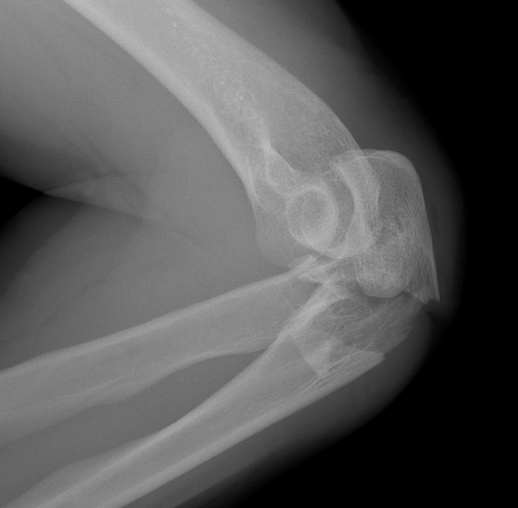

Proximal articular portion of the ulna

- greater sigmoid notch articulates with trochlea

- has a central bare area

- flexion / extension

Triceps insertion

- attaches to olecranon

- displaces olecranon fragment superiorly